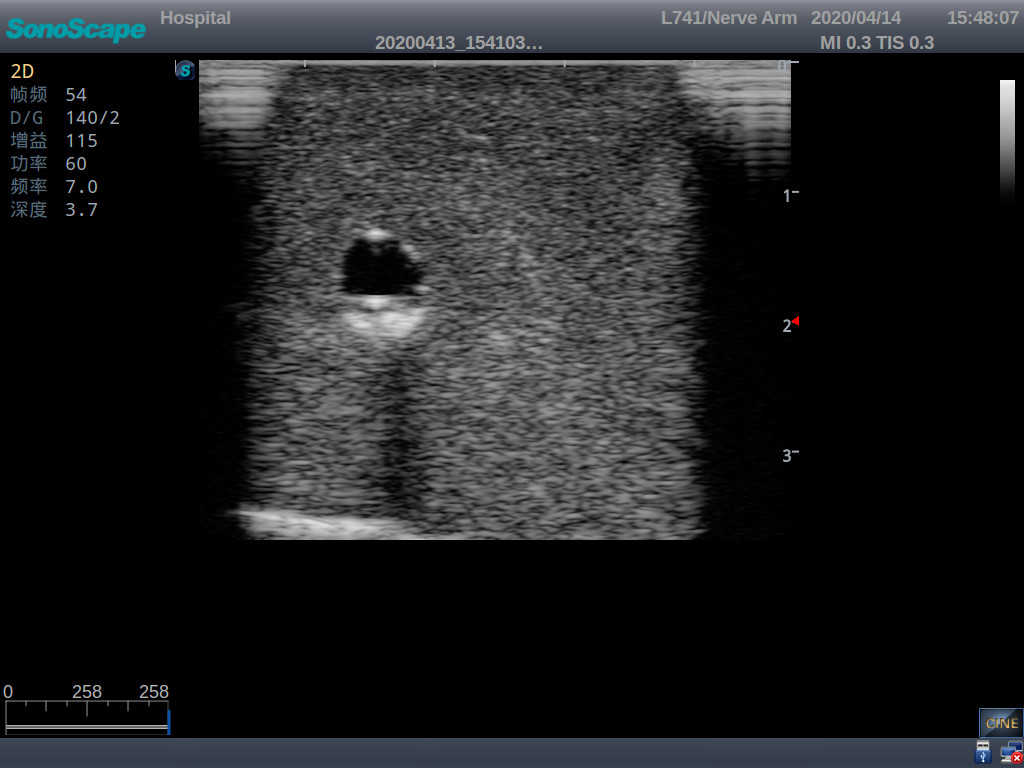

PICC Ultrasound Training Model

Model TYE1510.1

Outline

It is a model covering up from lobulus auriculae plane to the umbilical plane, and it has anatomical structures like clavicle, rib, sternocleidomastoid, jugular vein and basilic vein.

1)   Made of high molecular polymer ultrasound material, close to the real skin

2)   It can be used by real ultrasound machines

3)   Clear and real images of the tissues and organs (basilic vein and superior vena cava)